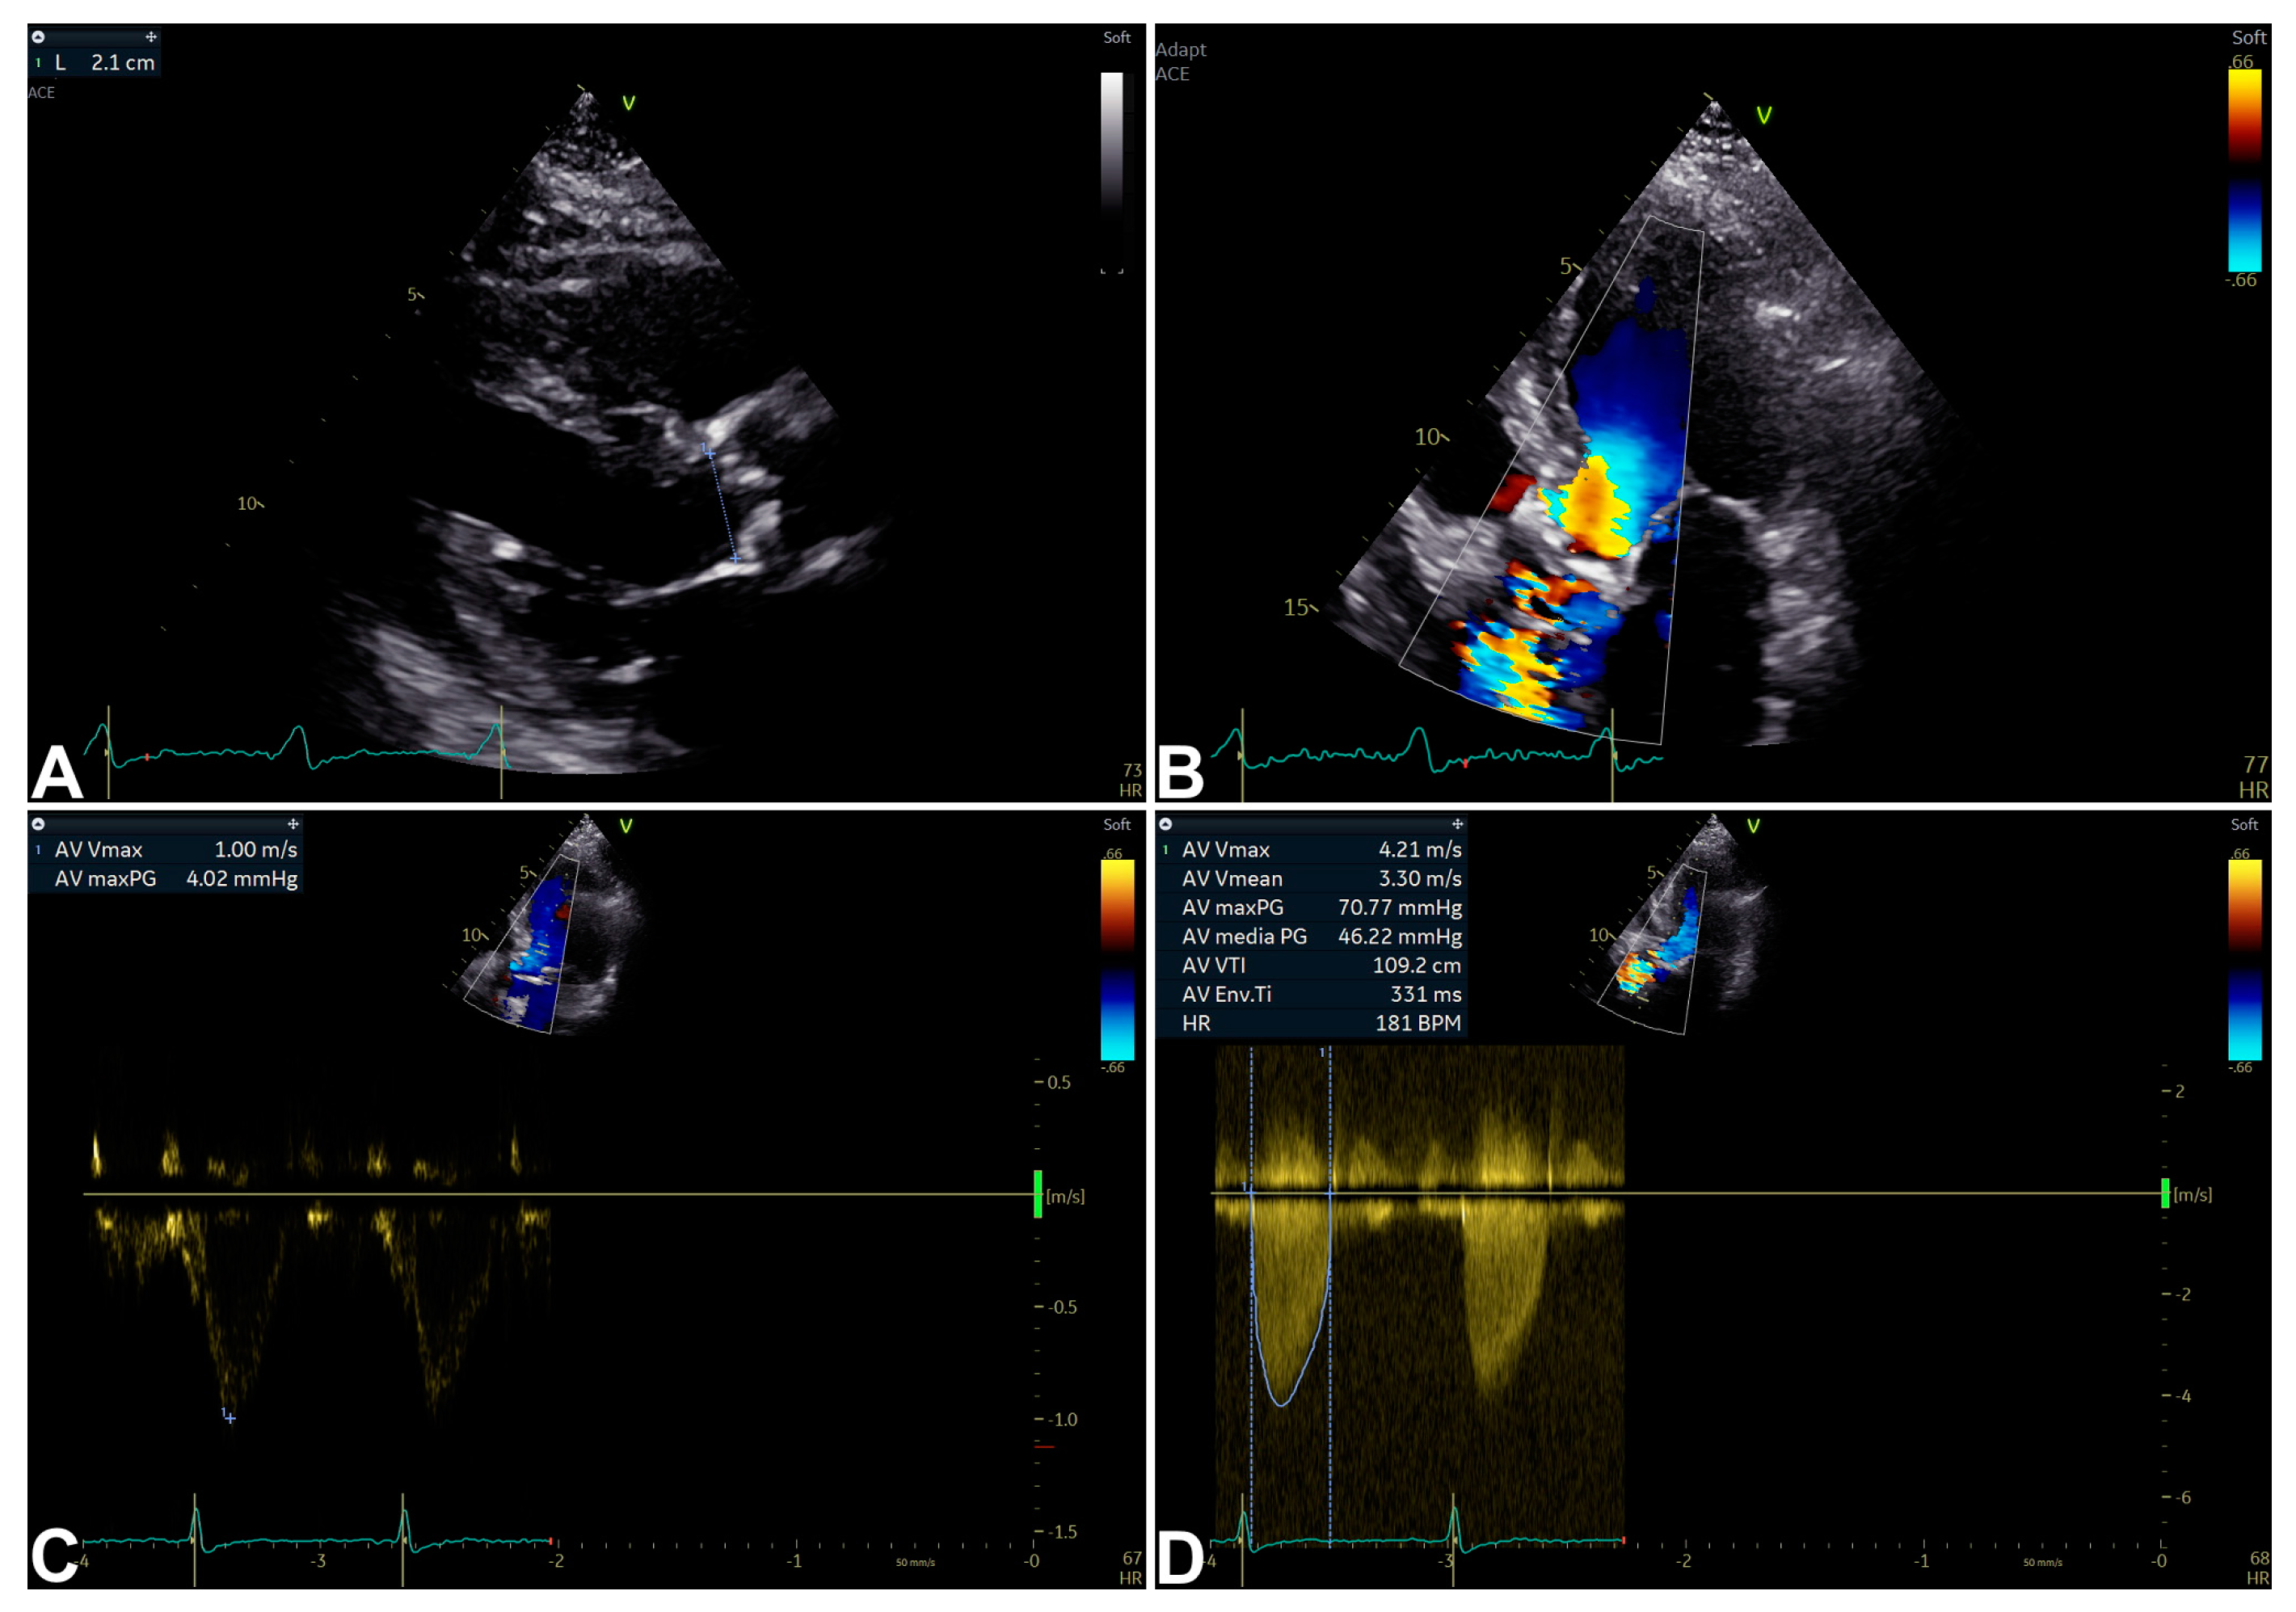

3. Echocardiography for Isolated Severe Aortic Stenosis Assessment and Characterization

| Parameter | Aortic Sclerosis | Mild AS | Moderate AS | Severe AS | Advantages | Limitations |

|---|---|---|---|---|---|---|

| Peak velocity (m/s) | ≤2.5 | 2.6–2.9 | 3.0–4.0 | ≥4 | - Direct measurement. - Strong predictor of clinical outcome. | - Flow-related. - US beam parallel alignment-related. |

| Mean gradient (mmHg) | None | <20 | 20–40 | ≥40 | - Units comparable to invasive measurements. | - Flow-related. - US beam parallel alignment-related. |

| AVA (cm2) | None | >1.5 | 1.0–1.5 | <1.0 | - Effective orifice area measurement. - Frequently feasible. - Relatively flow-related. | Measurement error more likely. |

| iAVA (cm2/m2) | None | >0.85 | 0.60–0.85 | <0.60 | - Effective orifice area measurement. - Frequently feasible. - Relatively flow-related. - More accurate than AVA. | Measurement error more likely. |

| Velocity ratio | None | >0.50 | 0.25–0.50 | <0.25 | - Less variability than AVA (Doppler-only required). | - Limited longitudinal data. - Ignores LVOT size variability. |